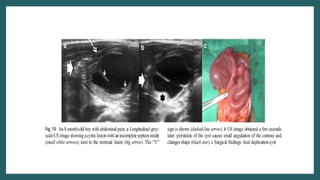

Ultrasound

• Typical gut signature sign present

• Wall is 2-3 mm thick

• Y sign(EDC share wall with adjacent GIT.

Caused by splitting of shared muscularis

propria between cyst and adjacent loop)

• Peristalsis present